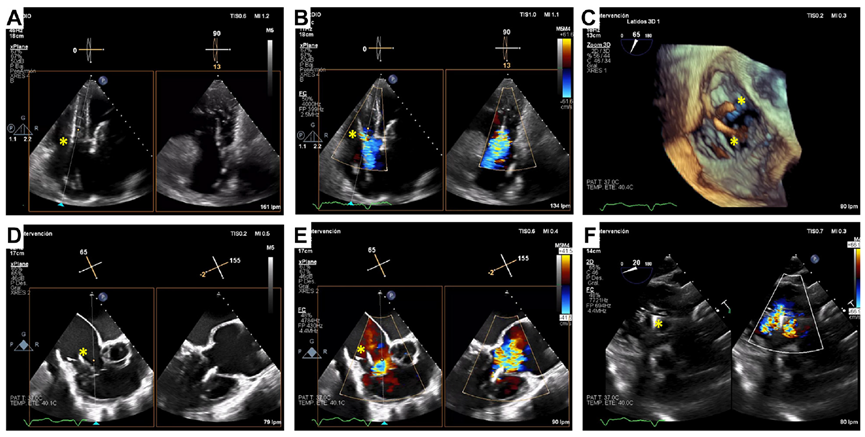

基線經(jīng)胸和經(jīng)食道超聲

術(shù)后經(jīng)食道超聲,僅微量瓣周漏